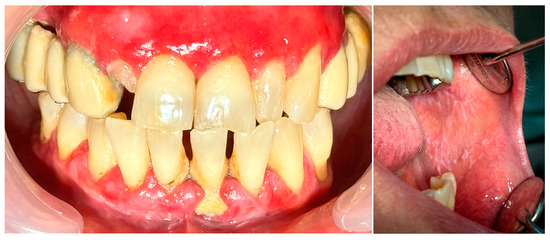

2.1. Clinical Case 1—Mucous Membrane Pemphigoid (MMP)